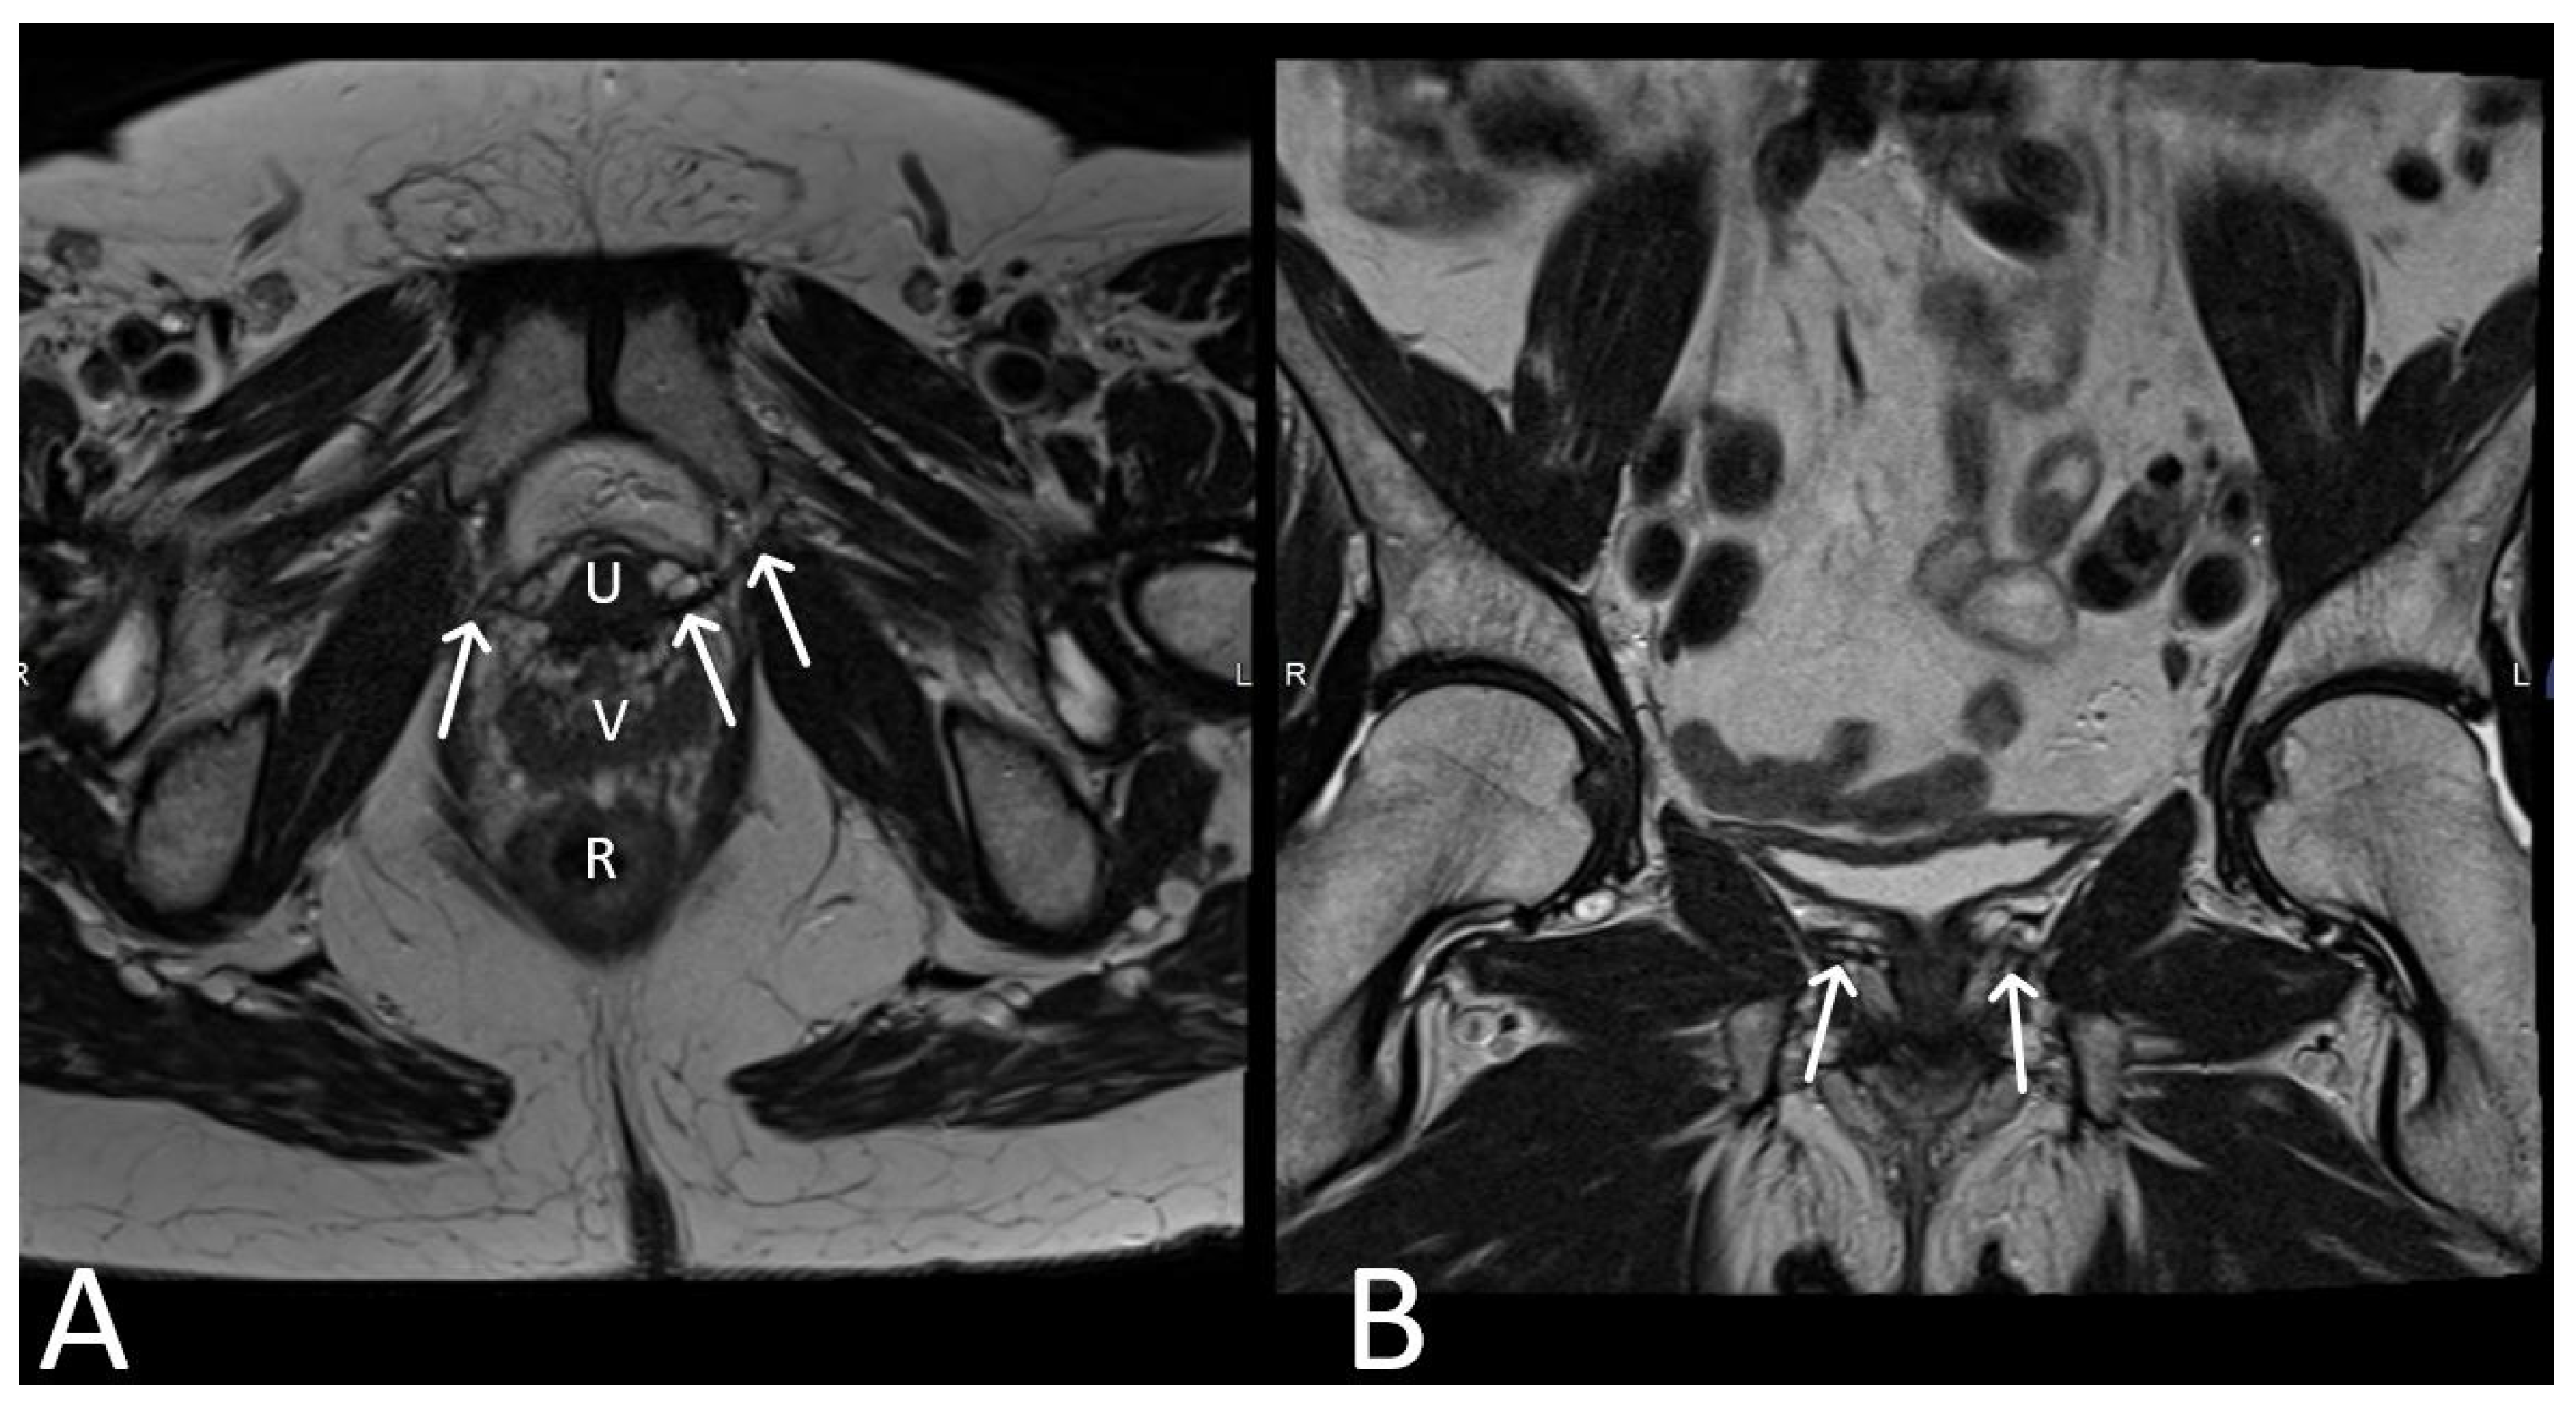

3. Normal Appearance of Urethral Meshes on MRI/CT